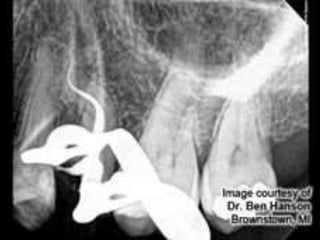

• Management of Curved Canals

A curvature of 20° in a narrow canal is almost

difficult to negotiate

whereas a curvature of 30° can be negotiated if

canal is wide.

 Ultimate challenge during instrumentation ,why?

• Ledge

• Perforation

• Strip perforation

• Transportaion

• Blokage of the canal

• Fracturing instruments

o Gradual curvature of the mesial canals in the

apical third.

o Acute curvature in the apical third.

o Curvature throughout the canal.

o Dilacerated root canal .

o S-shaped root canal.